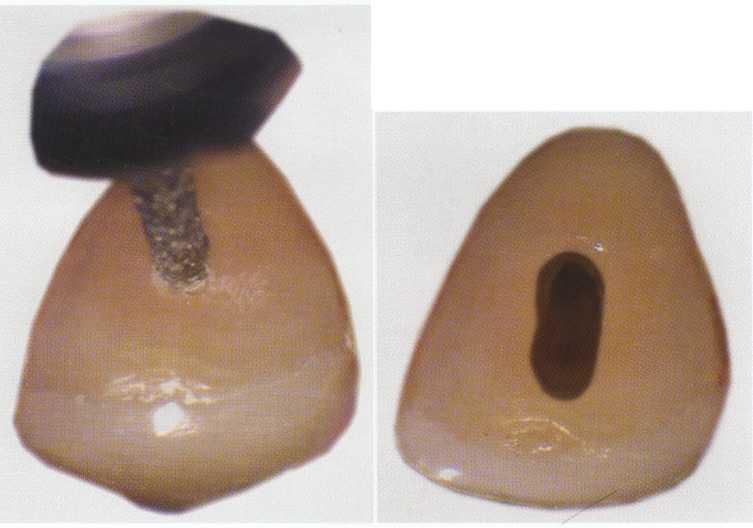

FIGURE 2-14 A, The lingual view shows the incisally repositioned access with the rotary notch. B, From the lateral view, the darker wedge-shaped portion of the access shows how incisally this notch may be placed. With the repositioned access, very little cervical dentin needs to be removed.

Maxillary Incisors

In uncomplicated cases, both maxillary central and lateral incisors share a common triangular-shaped access from the lingual surface of the tooth. The classic access design places the access centrally on the lingual surface between the incisal edge and the cervical edge7 ( Figure 2-14). This design is reflective of the poor restorative choices available in the past as well as the limited options for "hiding" the access more cervically. Such a design results in a much larger amount of dentin removal at the lingual cervical edge to gain straight-line access. With improved esthetic bonded composites, the classic access form can be modified by placing it considerably more incisally (Figure 2-15). The initial penetration should be approximately in the middle of the lingual surface of the tooth, not just above the cingulum as has been previously described.' After locating the canal, the clinician uses a long, tapered diamond to extend the access even further incisally and laterally. An additional modification for use with rotary instrumentation is to slightly notch the middle of the incisal extent of the access (see Figure 2-15). This allows even better straightline access and greatly decreases the potentially catastrophic cervical flexure of the rotary instruments that can contribute to premature, unexplained fracture.